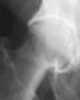

Malunited fracture of femoral neck

Coxa vara